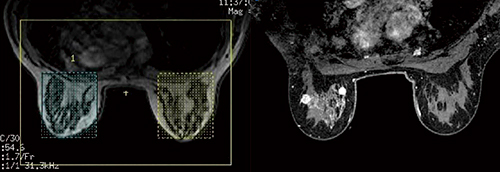

乳腺MR検査において,脂肪抑制効果を高めることは重要です。SIGNA Worksでは,左右個別にシミング領域(シムボリューム)を設定できるデュアルシム機能だけでなく,腋下などの脂肪抑制を効果的に行う2point-Dixon法“Flex”が併用可能です(図1)。このFlexは,region growing法によるフィールドマップを用いて磁場不均一の補正を行うことで,脂肪抑制効果を高めることが可能で,2D高速SE法(FSE-Flex),3Dボリューム撮像(Cube-Flex,VIBRANT-Flex)に併用可能です。また,動きに強いパラレルイメージングとノイズ低減技術が融合した“HyperARC”を併用することができます。さらに,Cube-Flexにおいては,圧縮センシング技術“HyperSense”を活用することで,画質を低下させることなく高速化が可能です。

図1 VIBRANT-Flex(デュアルシム機能と撮像例)